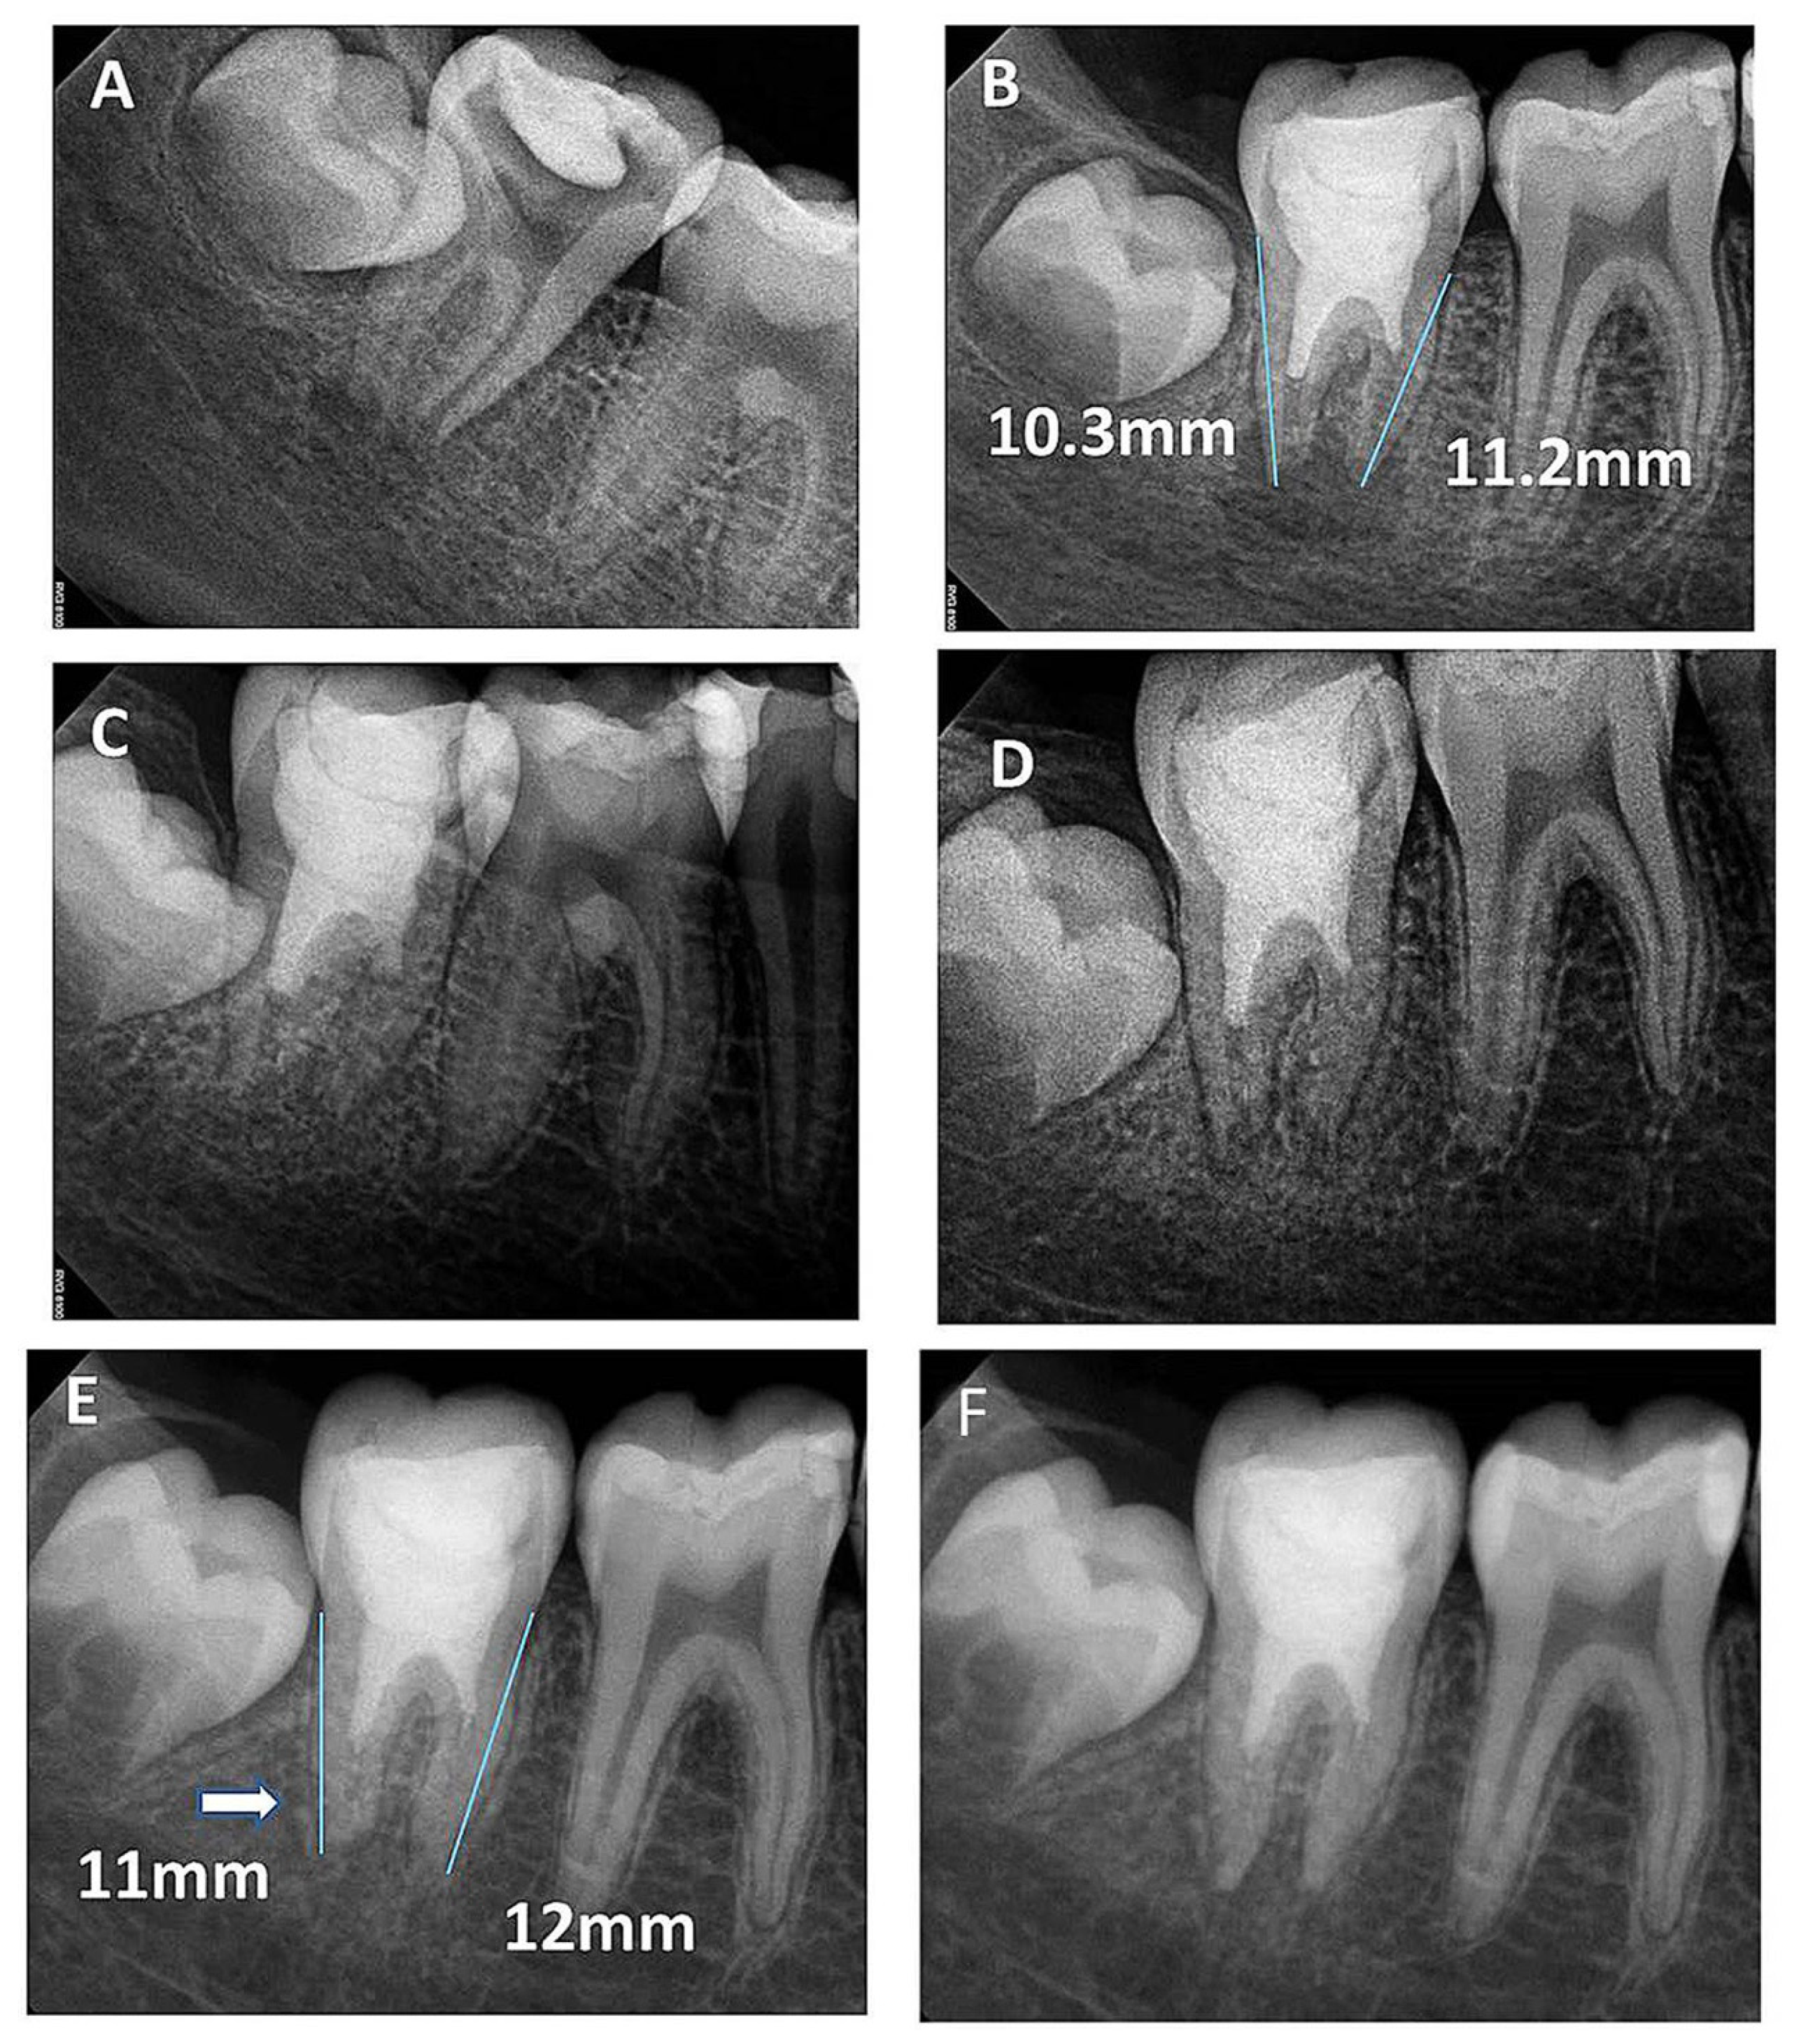

| Follow-Up Time | Median at Each Follow-Up Time (mm) | ||

|---|---|---|---|

| Root Length | Apical Canal Width | Dentin Wall Thickness | |

| Preoperative | 10.36 | 1.14 | 0.48 |

| 6th Month | 10.47 | 1.15 | 0.72 |

| 12th Month | 10.64 | 1.28 | 0.74 |

| 2nd Year | 10.79 | 1.29 | 0.76 |

| 3rd Year | 10.92 | 0.65 | 0.86 |

| 8th Year | 11.4 | 0.24 | 0.98 |